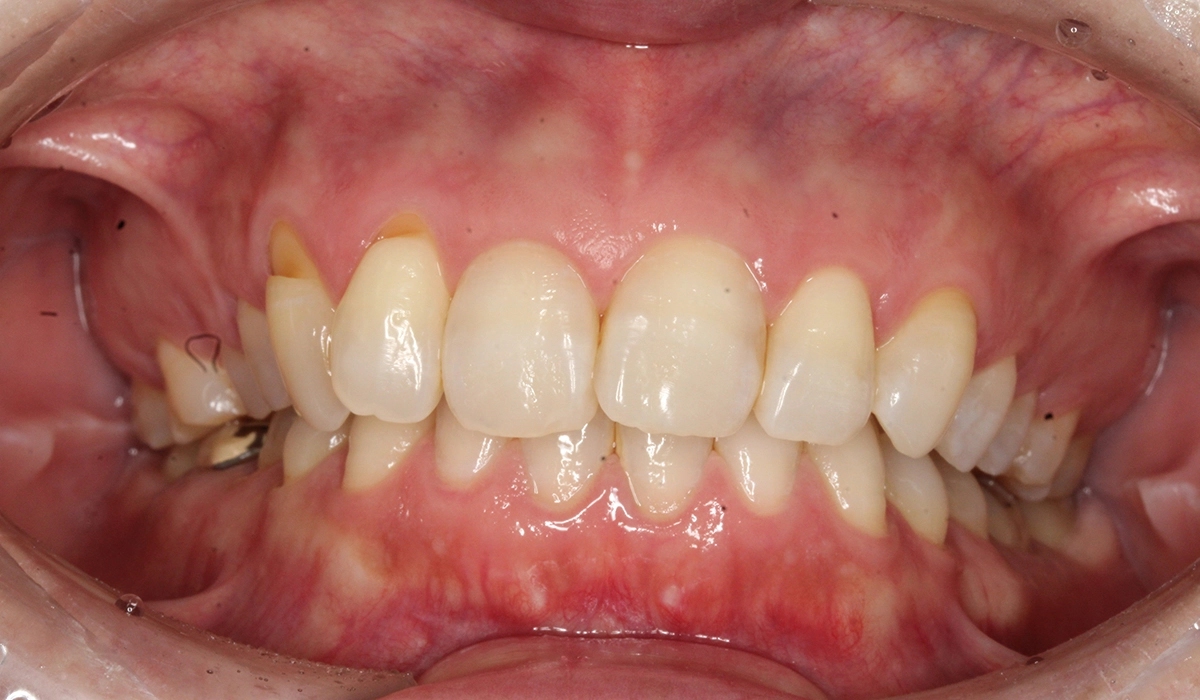

術前:正面